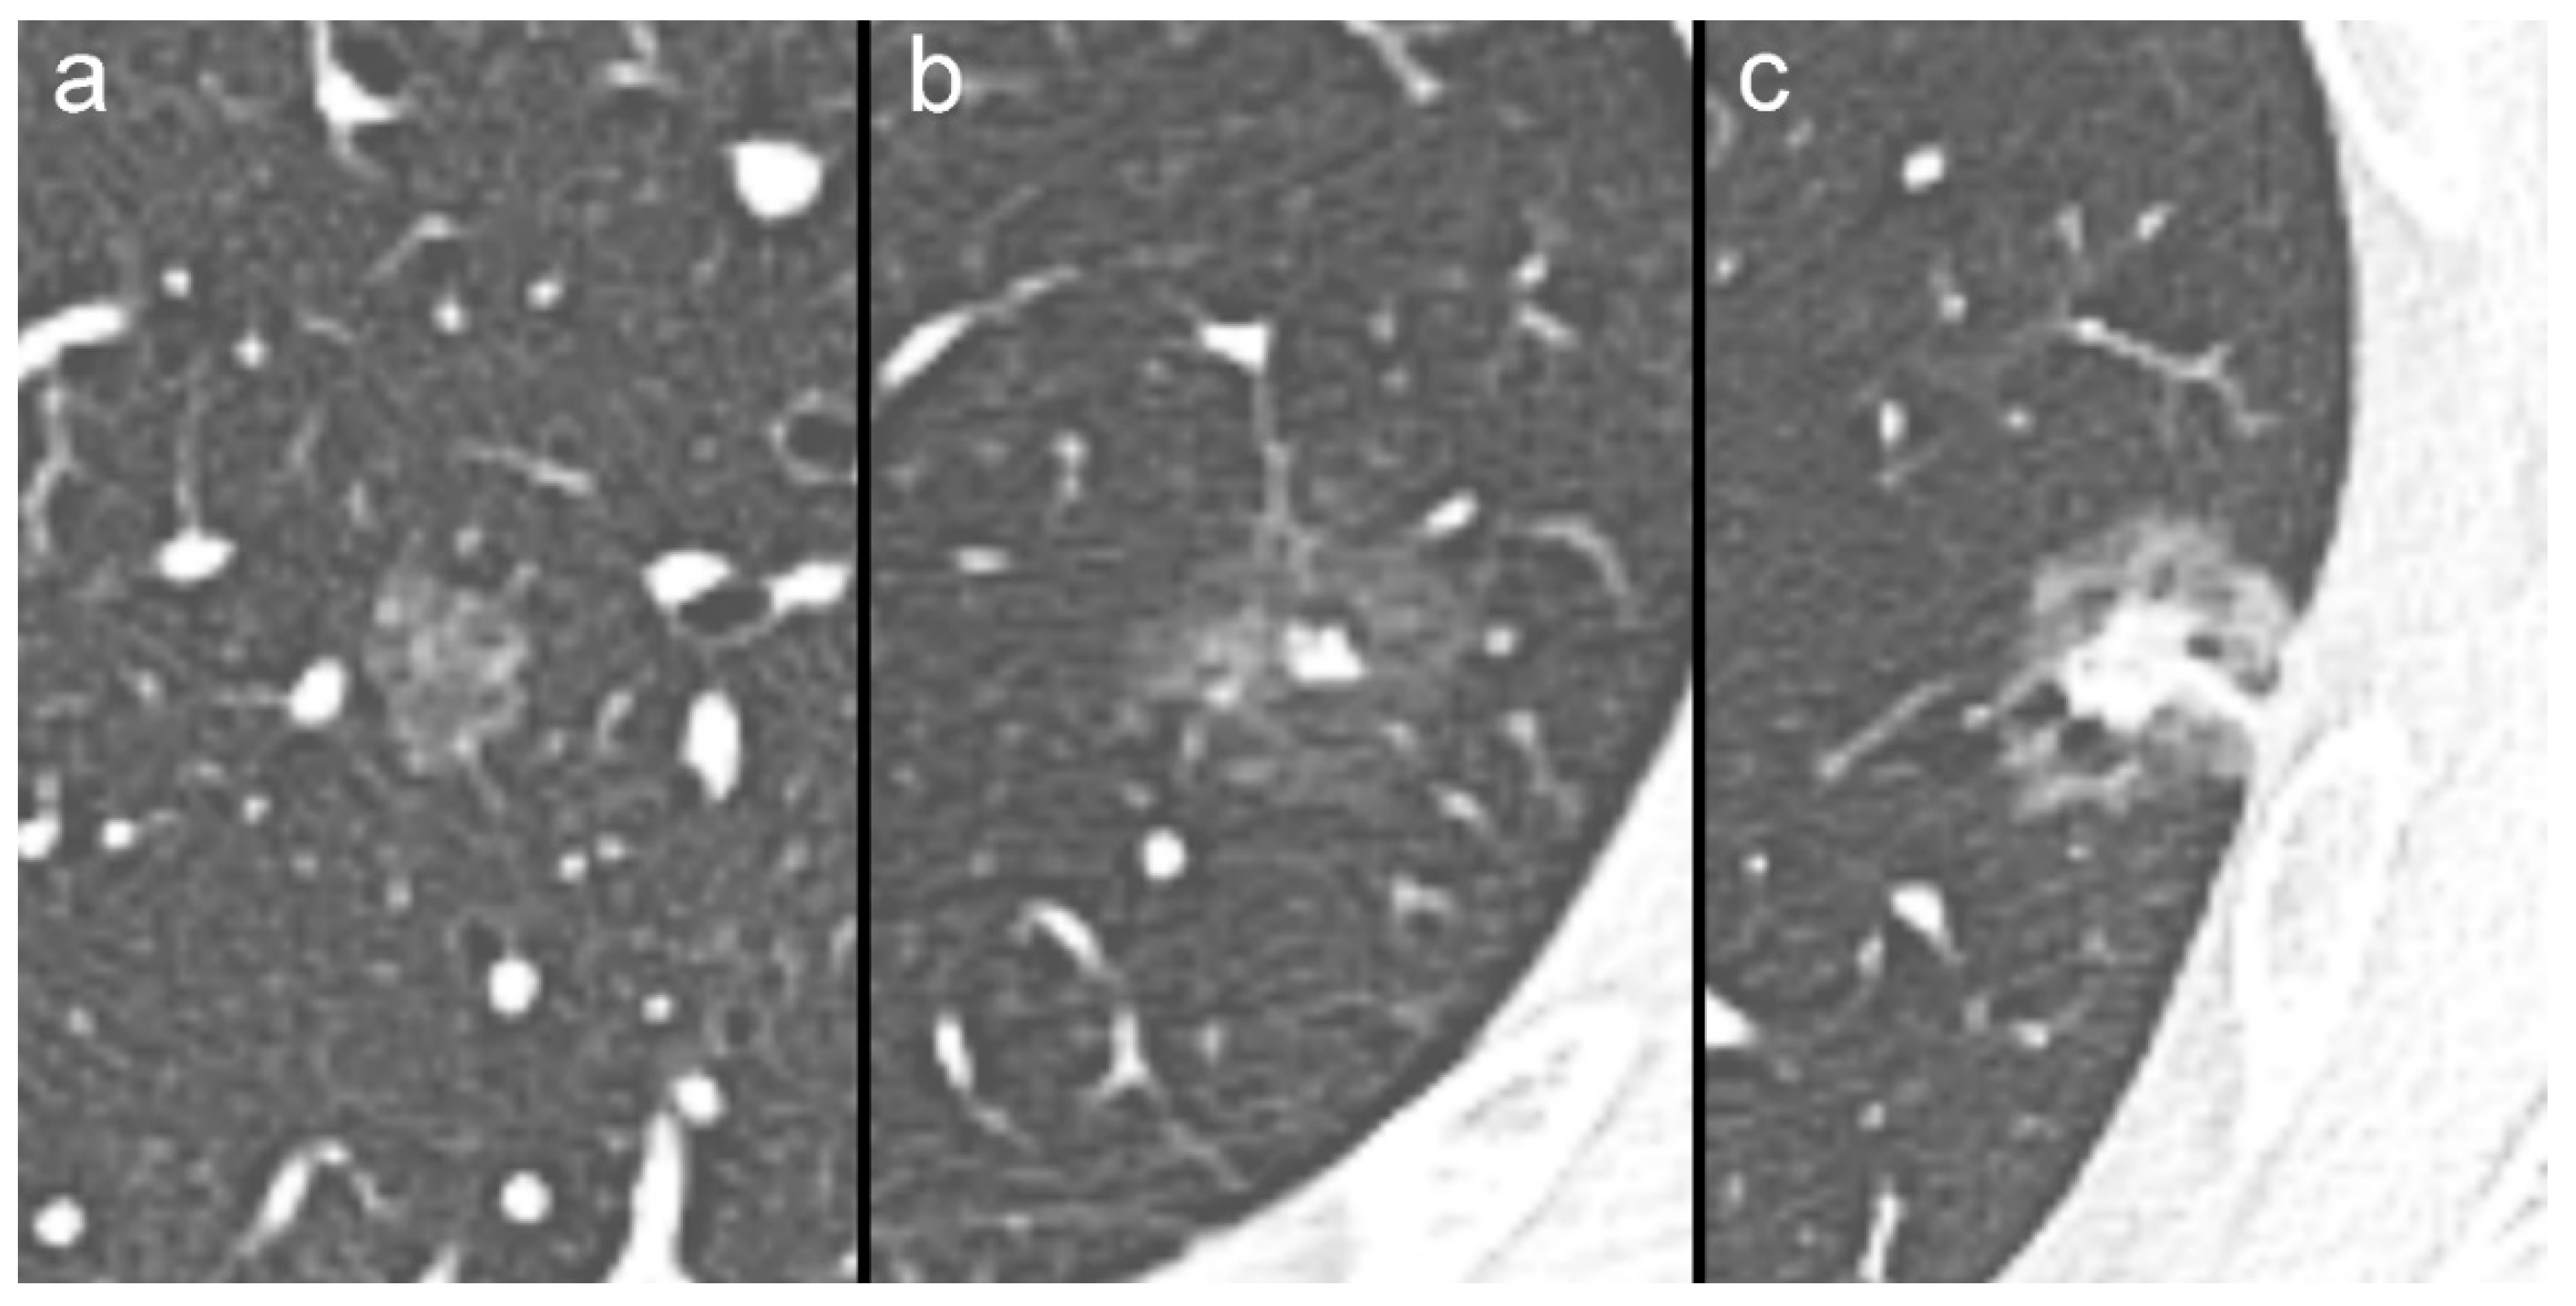

SSNs can be the expression of both benign and malignant lesions, such as inflammation, organizing pneumonia/focal interstitial fibrosis, or pre-invasive and invasive neoplasms [8,9,10]. SSNs are conventionally divided into non-solid (NSNs) and part-solid nodules (PSNs) according to the absence or presence of an intralesional solid component (Figure 1) [11,12]. PSNs can be further classified into two or three different groups according to the size of the intralesional solid component (Figure 1) [11,12,13].

Figure 1.

Cropped axial computed tomography (CT) images showing the different subtypes of pulmonary subsolid nodules: (a) non-solid nodule; (b) part-solid nodule with small solid component (less than 6 mm in diameter); (c) part-solid nodule with a large solid component.

In these different groups of SSNs, the risk of aggressive behavior is strongly associated with the presence and size of the intralesional solid component [11,12,13,14]. Therefore, the updated Fleischner Society and Lung CT Screening Reporting and Data System (Lung-RADS) guidelines recommend different management for these different SSN subtypes [11,13].

Regardless of the route of presentation (clinical practice or lung cancer screening), SSNs with a solid component less than 6 mm in diameter (Figure 1a,b) are considered to have a very low or low probability of becoming aggressive cancer [13]. Therefore, conservative management with CT surveillance is justified for this subtype of SSN [11,12,13,14].

On the other hand, SSNs with a solid component greater than 6 or 8 mm (Figure 1c) are considered suspicious or very suspicious, with a high probability to be or to become aggressive cancers. In this last scenario, a more aggressive approach with additional imaging tests (such as CT at three to six months and/or PET/CT), nonsurgical tissue sampling, and/or surgical resection should be recommended, particularly for SSNs with suspicious morphology, such as irregular or spiculated margins and intralesional bubbly lucencies [11,12,13].